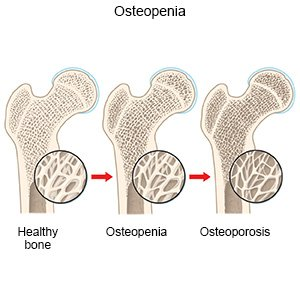

Learn about the causes of osteoporosis, key risk factors, and how to prevent bone loss. Get expert orthopedic insights for better bone health.

Bone health is vital at every age. Many people think only the elderly need to worry about bones, but that’s far from the truth. Everyone